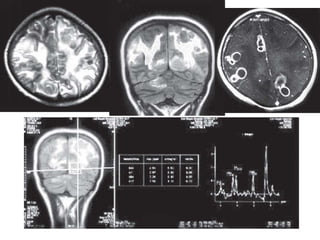

Axial T2W MR (A) and FLAIR Coronal image (B)

showing multiple conglomerate lesions

hypointense on T2W in the right parietal

region with surrounding edema. Mass effect

noted on the ipsilateral right lateral ventricle

with shift of the midline to the contralateral

side. On contrast

enhancement (C) conglomeration and ring

enhancement of the lesions seen—Multiple

tuberculomas.

MR spectroscopy

• shows prominent lipid peaks in tuberculomas

• Caseous material typical of tuberculomas has

a high lipid content .This spectral pattern is

highly specific for tuberculomas